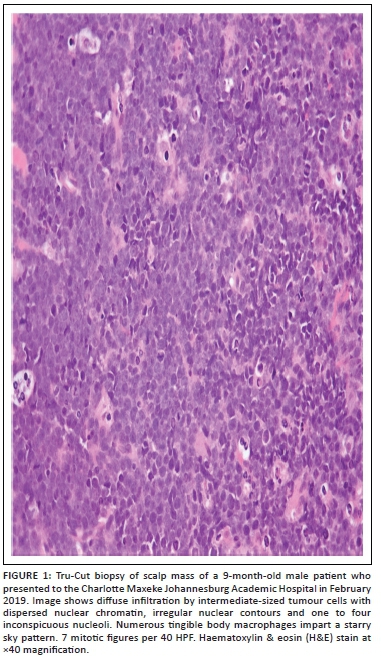

Histological examination of the Tru-Cut biopsy of the scalp mass revealed intermediate-sized tumour cells with irregular nuclear contours, a high nuclear-cytoplasmic ratio, dispersed nuclear chromatin, and one to four inconspicuous nucleoli present within a prominent background of tingible body macrophages (Figure 1). The tumour immunophenotype based on flow cytometry and immunohistochemistry was that of a precursor B-cell, with the expression of TdT, absence of surface light chains and a high Ki67 index (Table 1, Table 2 and Figure 2). Contrastingly, the high S-phase fraction detected was in a range that is typically seen in Burkitt leukaemia.6 Given the latter, Fluorescence in-situ hybridisation analysis was requested and found to be positive for the translocation t(8;14)(q24;q32) (Figure 3).